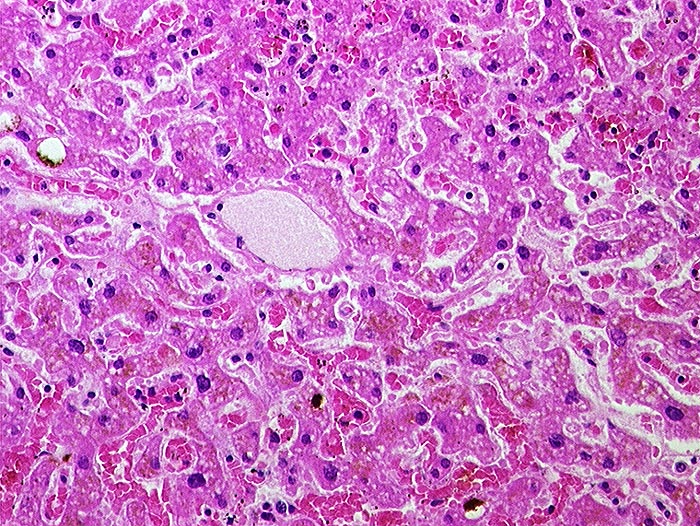

Subakute Stauung der Leber

Leber HE

Pathologischer Befund